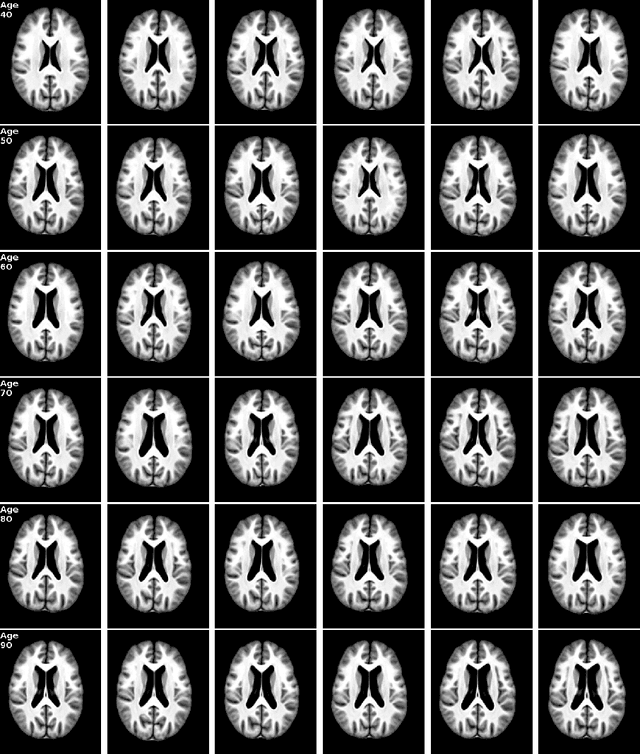

Abstract:Brain aging is a widely studied longitudinal process throughout which the brain undergoes considerable morphological changes and various machine learning approaches have been proposed to analyze it. Within this context, brain age prediction from structural MR images and age-specific brain morphology template generation are two problems that have attracted much attention. While most approaches tackle these tasks independently, we assume that they are inverse directions of the same functional bidirectional relationship between a brain's morphology and an age variable. In this paper, we propose to model this relationship with a single conditional normalizing flow, which unifies brain age prediction and age-conditioned generative modeling in a novel way. In an initial evaluation of this idea, we show that our normalizing flow brain aging model can accurately predict brain age while also being able to generate age-specific brain morphology templates that realistically represent the typical aging trend in a healthy population. This work is a step towards unified modeling of functional relationships between 3D brain morphology and clinical variables of interest with powerful normalizing flows.